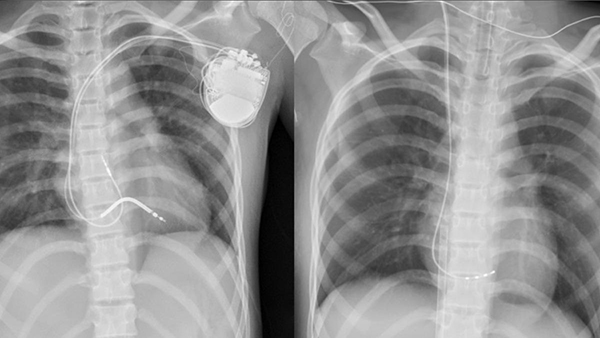

而戴以信表示,已帮小涵装设体内去颤器,以防心律不整时电击救命,并规则服药控制,她住院1个月后出院,重回校园上学,没有留下脑缺氧、认知功能异常等后遗症。中医大儿医儿童及超音波中心副院长谢凯生也提醒,孩童遇到不明原因“晕厥”或“抽搐”,应尽速至医疗院所儿童心脏科就医,检查是否有尚未发现的心律不整,并接受适当的治疗。